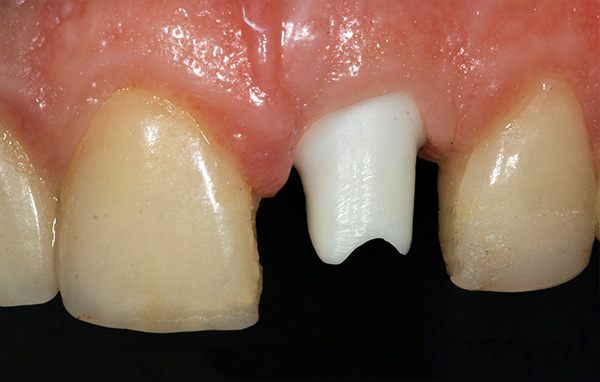

É assim que um pilar individual feito de zircônia montado em um implante se parece com: